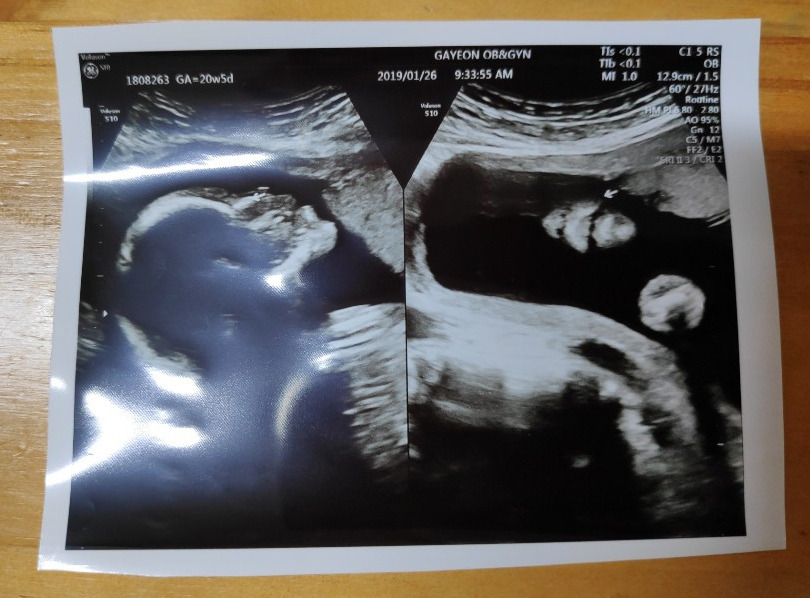

꼬톨이의 손과 발, 뇌, 장기 등이 정상적으로 자리 잡아가고 있는지를 보는 2차 정밀 초음파날!

초음파실에 들어가 하나하나 꼼꼼히 꼬톨이의 모습을 확인했다.

무엇보다도 기뻤던 것은 꼬톨이의 성별을 알게 된 것

지난번 진료 때도 알지 못했던 우리 꼬톨이의 성별은 공주님이었다!